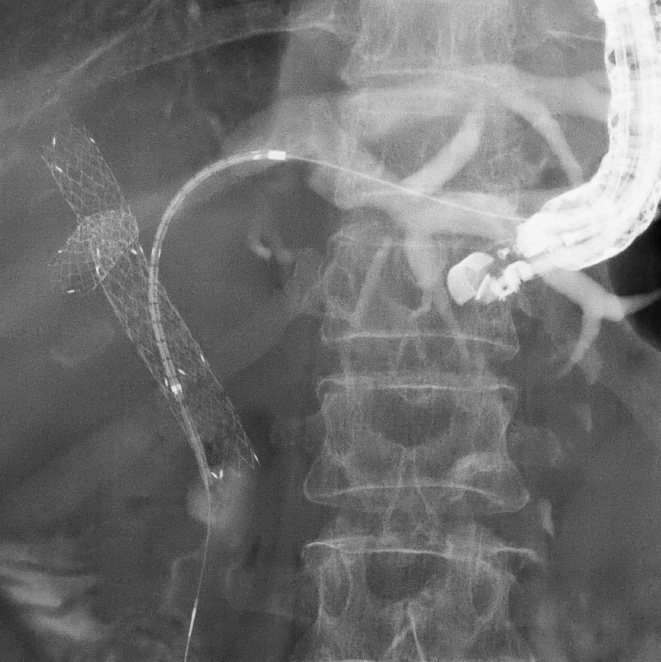

- 進行大腸がんイレウスに対する ステント治療(Bridge to Surgery)

- 進行癌に伴う通過障害に対する 消化管ステントによる緩和治療

肝門部胆管癌に対するEUS下胆道ドレナージ

急性胆嚢炎に対するEUS下胆嚢ドレナージ(LAMS留置)